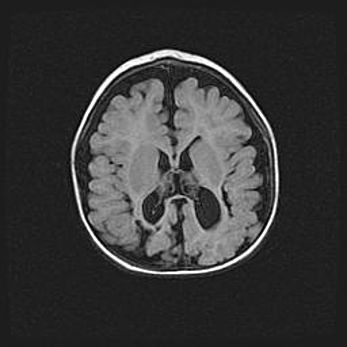

Церебральная ишемия II.

Возраст: 5 дней

Вес: 3400 г

Пол: женский

Окружность головы: 35 см

Срок гестации: 39 недель

Церебральная ишемия – это заболевание, характеризующееся недостаточностью (гипоксией) либо полным прекращением (аноксией) снабжения мозга кислородом по причине закупорки одного или нескольких сосудов. Это приводит к  что метаболическим расстройствам различной степени тяжести в тканях головного мозга, развитию коагуляционных некрозов и гибели нейронов.